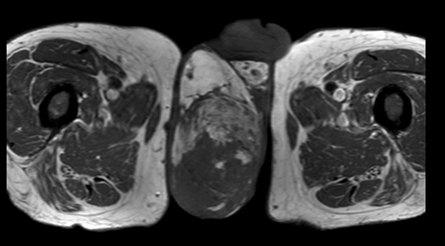

A 55-year-old male diagnosed with prostate cancer in 2010 and underwent radical prostatectomy followed by salvage radiation therapy to the prostatic fossa. He was found to have bone metastasis and since had been treated with hormonal therapy, enzalutamide, abiraterone, radium-223, and taxotere. In April 2016, the patients PSA was >1500 ng/dl. In August 2016, the patient,s was found to have bone marrow involvement with anemia (hemoglobin 6.1 g/dL) and thrombocytopenia (platelets 32x103/ul). In November 2016, the patient began complaining of scrotal pain. Physical examination demonstrated an enlarged scrotum with palpable mass and magnetic resonance imaging (MRI) scan revealed a right testicular hydrocele containing multiple enhancing nodules (Figure 1) (Figure 2) (Figure 3) (Figure 4). At last follow-up on November 10, 2016, the patient continued to have scrotal pain, and required transfusions for anemia and thrombocytopenia and is currently being treated with carboplatin and cabazitaxel.

Cursor on image to zoom/Click text to open image

Figure 4: T1 magnetic resonance imaging scan axial view showing enlarged right testicle occupying most of the scrotal space.